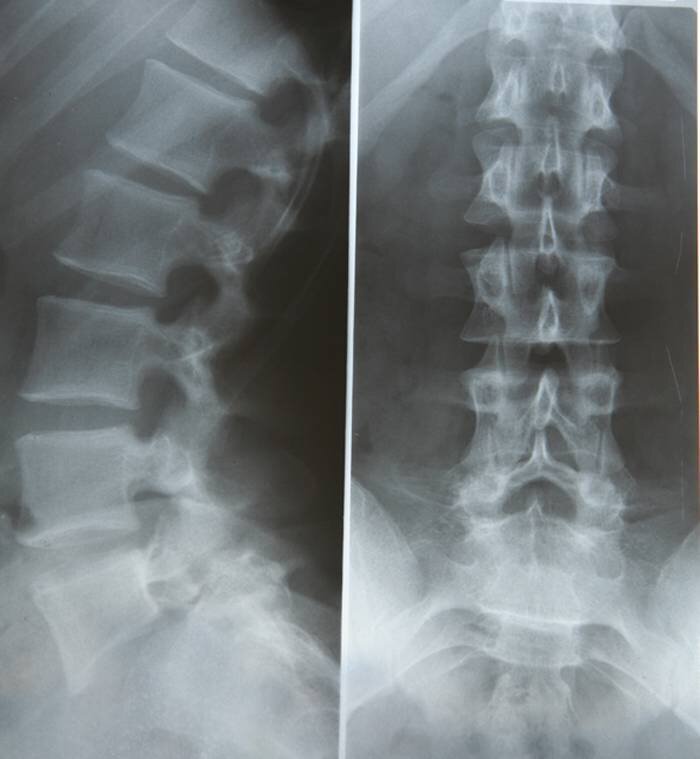

Рентгенологическое обследование ("рентген") очень информативен при травмах, допустим после переломов костей. Его не рекомендуется делать часто, при дегенеративно-дистрофических изменениях (остеохондрозе) позвоночника его достаточно делать 1 раз в год. При переломах же, после травмы для верификации диагноза и соответственно после снятия гипса, а также по назначению врача.